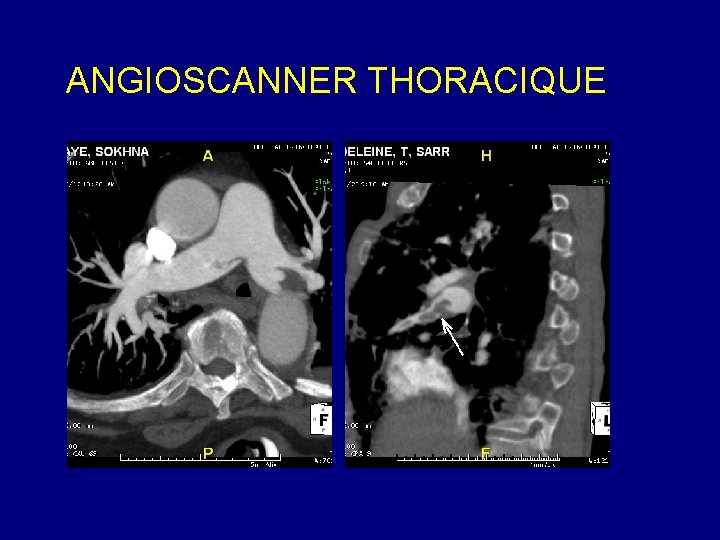

ANGIO SCANNER THORACIQUE Etude de l’aorte Etude des artères pulmonaires Anévrisme dissection Embolie pulmonaire Evaluation des cardiopathies congénitales

ANGIOSCANNER THORACIQUE